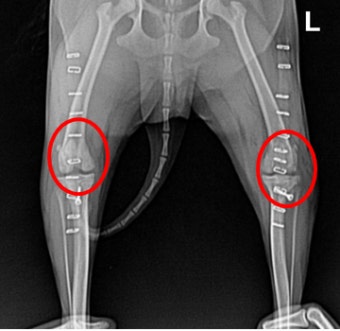

8. 슬개골 탈구 치료 방법

1~2등급의 경우에는 비수술적 요법(물리치료, 체중조절)도 가능합니다.

3~4등급이라면 대부분 수술을 권장해요. 관절을 제자리에 고정하고 연골 손상을 줄이기 위해서죠.